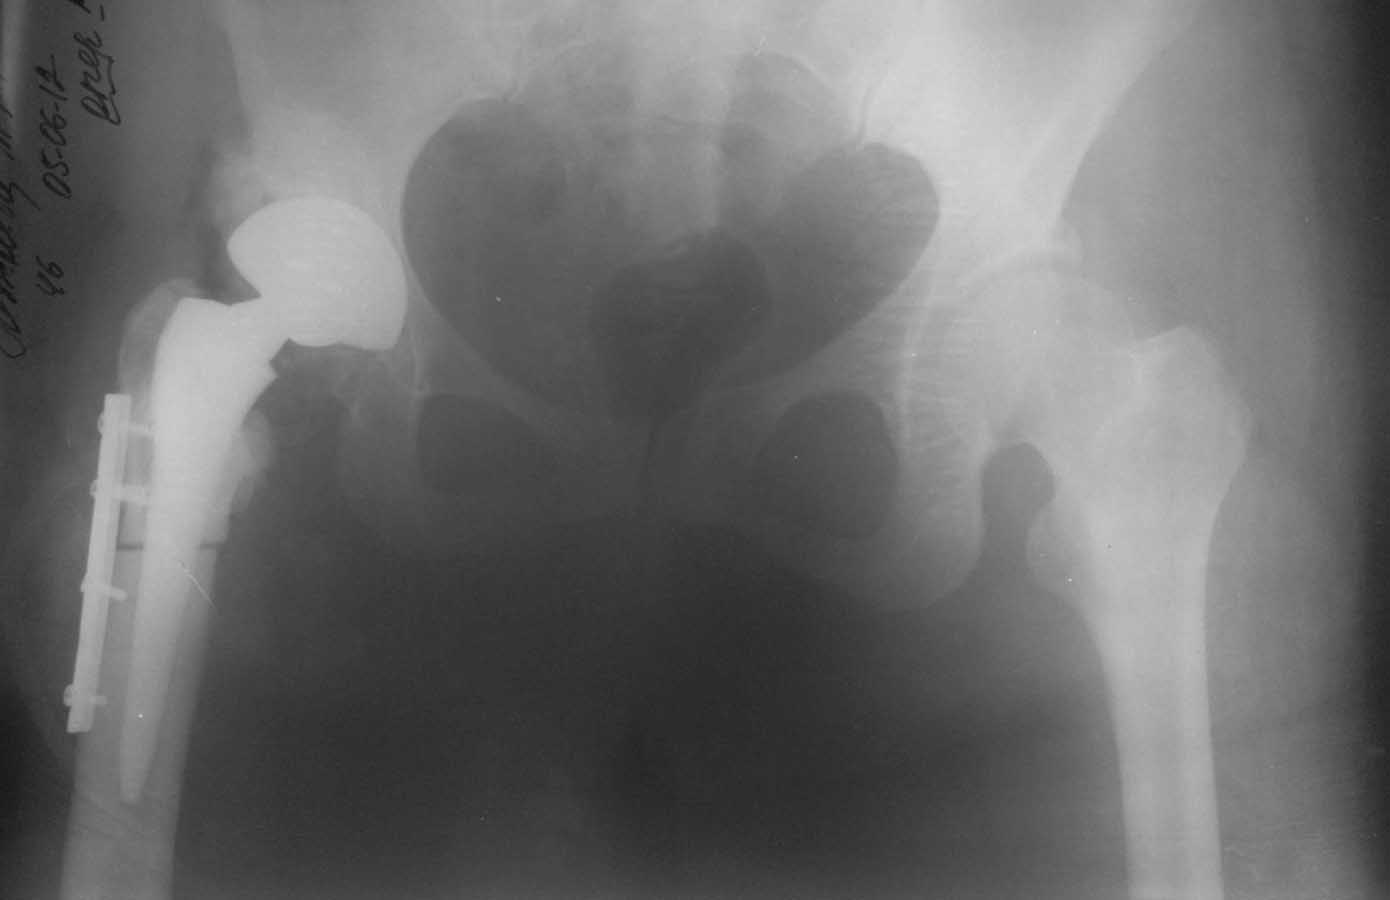

Уважаемые коллеги, к нам поступила женщина 45 лет с такой вот ситуацией:

Операция около 1,5 месяцев назад: тотальное б/ц эндопротезирование с остеотомией проксимального отдела бедра. Послеоперационный период - без особенностей, рана зажила первично, выписана домой. В анамнезе в детском и юношеском возрасте несколько оперативных вмешательств на вертлужной впадине и бедре по поводу врожденного вывиха бедра, судя по рубцам, протекавшие не совсем гладко.